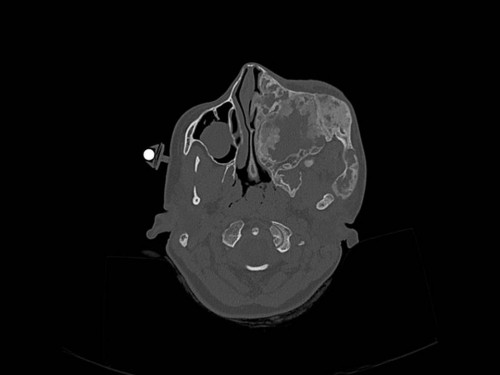

Eine 16-jährige Patientin kommt in eine MKG-chirurgische Praxis zur Abklärung der weiteren Vorgehensweise bzgl. ihrer Erkrankung.

Sie betrachten die angefertigten Röntgenbilder. Welche der folgenden Röntgenbefunde ist korrekt? Ossäre Auftreibungen im Bereich …

- A… der Mandibula links.

- B… des Os frontale links.

- C… des Os zygomaticum links.

- D… des Os temporale links.

- EAlle genannten Aussagen sind korrekt.

Bildgebung - OPAN 2004